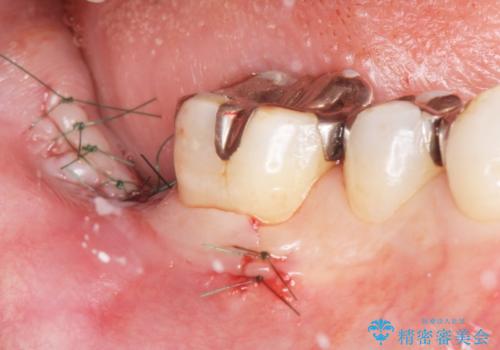

- インプラントをできるだけ安く入れたいとご希望され来院された患者様です。

予算は抑えたいが確実でしっかりとした治療を受けたいとの事でした。

レントゲン及びCTを撮影し骨の状態を確認したのち、アルファタイトインプラントによる治療を行いました。

- 外科手術のため、術後に痛みや腫れ、違和感を伴います